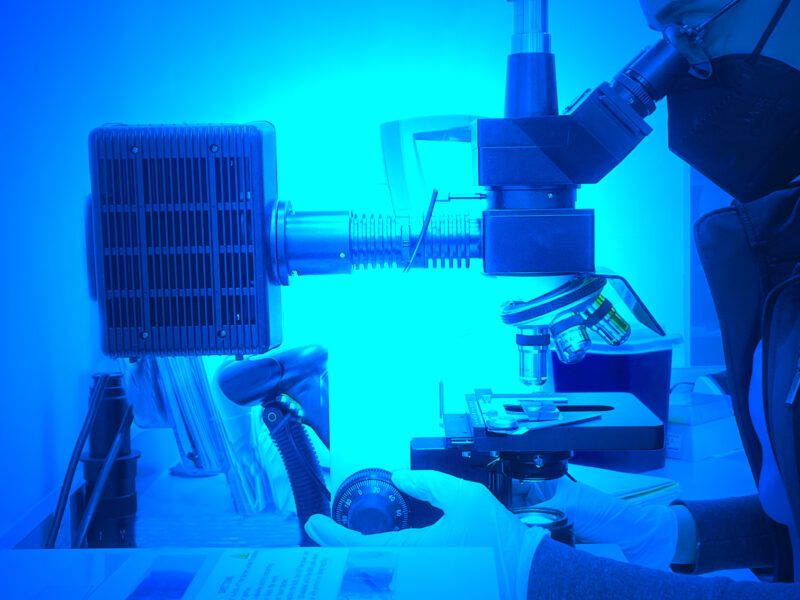

Contamos con una amplia gama de servicios y pruebas de análisis molecular y seguimos creciendo con tecnologías de última generación, es por eso que todas nuestras pruebas son analizadas en nuestras instalaciones, evitando los riesgos que implica el envío de muestras fuera del estado.